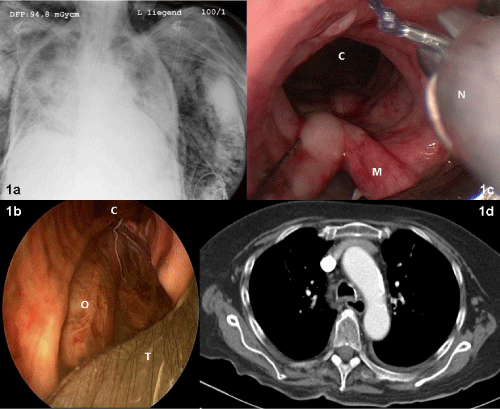

Immediately after the emergency intubation, a severe mediastinal and subcutaneous emphysema appeared and a tracheal laceration was diagnosed by bronchoscopy. The tube was placed distally of the lesion but could not prevent further progression of subcutaneous emphysema. Catecholamines and broad spectrum antibiotics were started. Based on repeated tube dislocations and difficulties to maintain adequate oxygenation, the decision was taken to repair the trachea. Nine hours after intubation and 4 hours after laparotomy, this woman was transferred to our hospital while intubated, with catecholamines and blurry infiltrates in both lungs seen on the chest X-ray (Figure 1a). A rigid bronchoscopy was done to exactly investigate the injury. It demonstrated a 6 cm full thickness rupture in the middle of the membraneous posterior wall, full of cloudy gastric contents (Figure 1b). With short interruptions of the jet ventilation, the complete rupture was washed and cleaned using normal saline >100ml. The rigid bronchoscopy was now changed with a 14mm rigid tracheaoscope. A running endotracheal suture with a 2/0 Vicryl thread (UCLX needle, Ethicon, Germany) was then applied with the optical needle holder (Karl Storz Endoscopes, Tuttlingen, Germany) (Figure 1c) as described earlier [5].

Figure 1a-d: Endobronchial findings and chest X-rays in the course of the treatment

The woman needed lung protective ventilation for 7 more days for a severe aspiration pneumonitis before she could be extubated. No further episode of tube obstruction occurred. After 5 days with repeated bronchoscopies for retention of secretions, she was exhausted and needed reintubation and early surgical tracheostomy. Despite the fact that the whole bronchial system was severely inflamed, the posterior tracheal wall healed primarily with no relevant fluid collection in the mediastinum (Figure 1d). The enteral nutrition was applied via nasogastric tube and later via percutaneous endoscopic gastrostomy. After 23 days, weaning from the ventilator was successful and the tracheostomy cannula could be removed at day 26. She was discharged in a home for elderly residents on day 47 and is fully mobile without complaints eight months later.